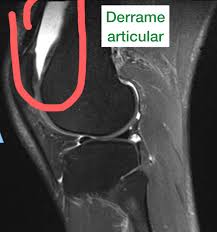

- Lesões articulares: condromalácia patelar, lesões de menisco, derrame articular.

Os protocolos de RM para lesões esportivas variam de acordo com a área a ser examinada, mas normalmente incluem sequências T1, T2, STIR ou PD Fat Sat, que permitem identificar tanto a anatomia normal quanto as alterações patológicas.